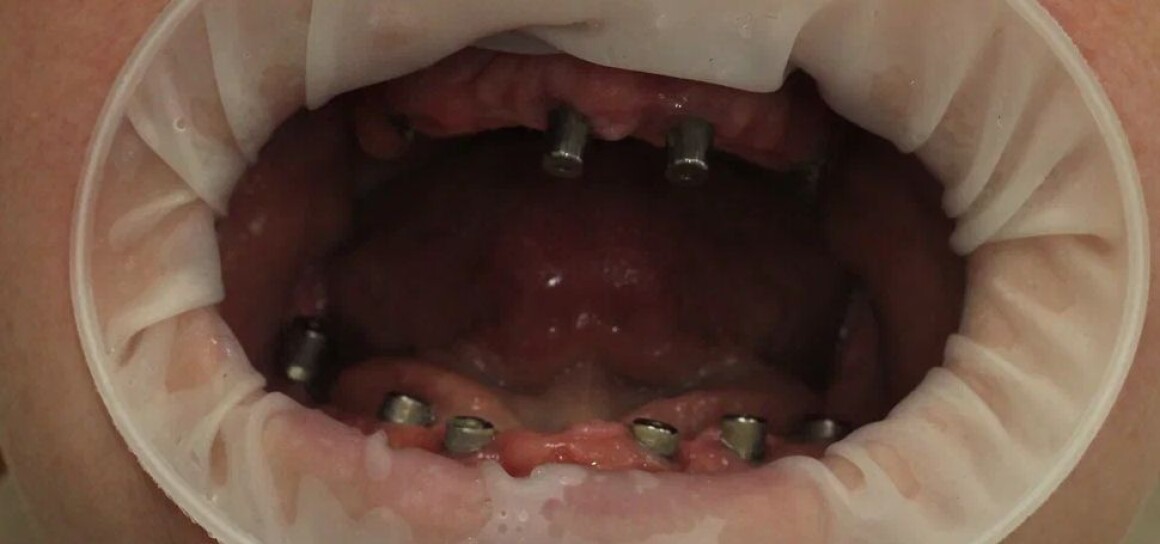

• Имплантация 12 имплантантов за один раз

• Установка временных коронок на имплантантах